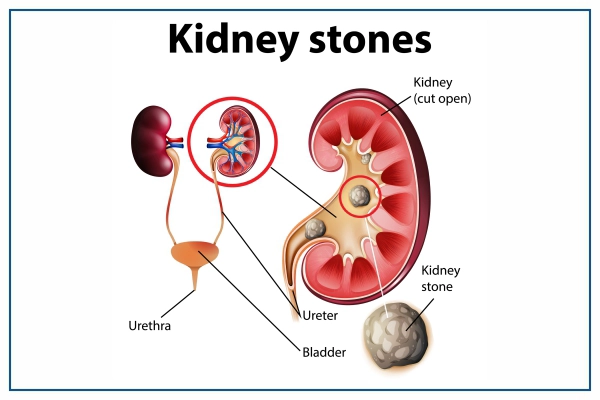

Kidney Stone Management